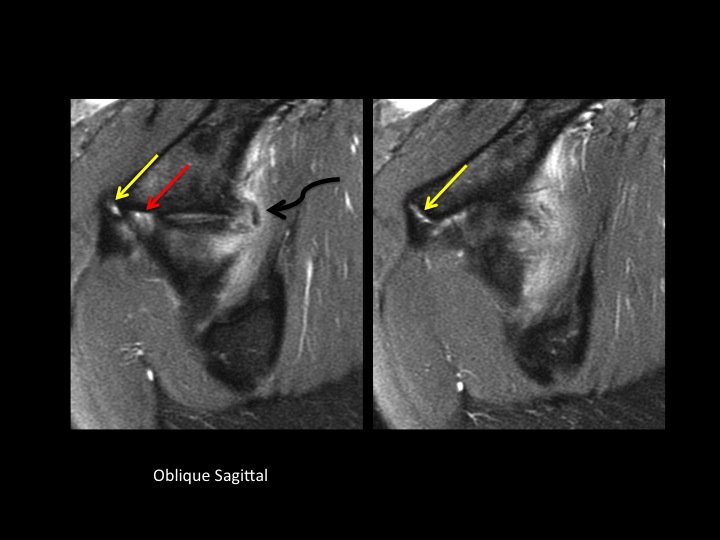

26F dancer with acute injury and hip pain

Yellow and Red arrows indicate partial tears at the origin of the direct and indirect head of the rectus femoris, respectively. The white arrowheads show acetabular stripping of the indirect head and iliofemoral ligament. I presume, due to the acuity of injury, that the dark amorphous signal (curved black arrow) is hemorrhage....but can I know that with certainty without either XR or US? I often have difficulty, particularly in shoulder, when I think there might be punctate calcific deposits that are unlikely to be visible by XR: would you recommend US in all such cases? (and, btw, I dont think the labrum is normal, but doubt thats her main problem...I suspect this will all heal with rest)